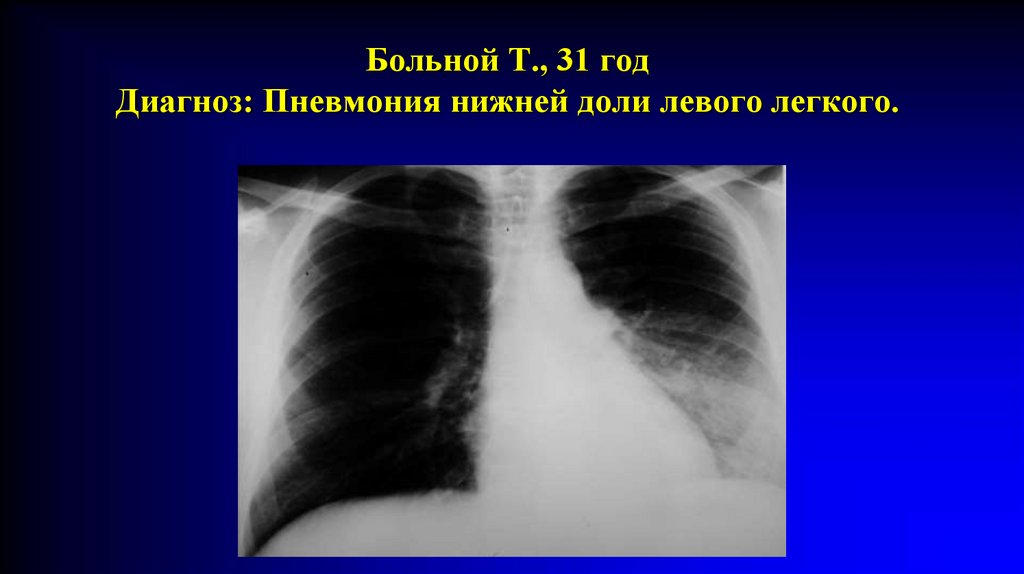

Больной Т., 31 год

Диагноз: Пневмония нижней доли левого легкого.

Томограмма того же больного.